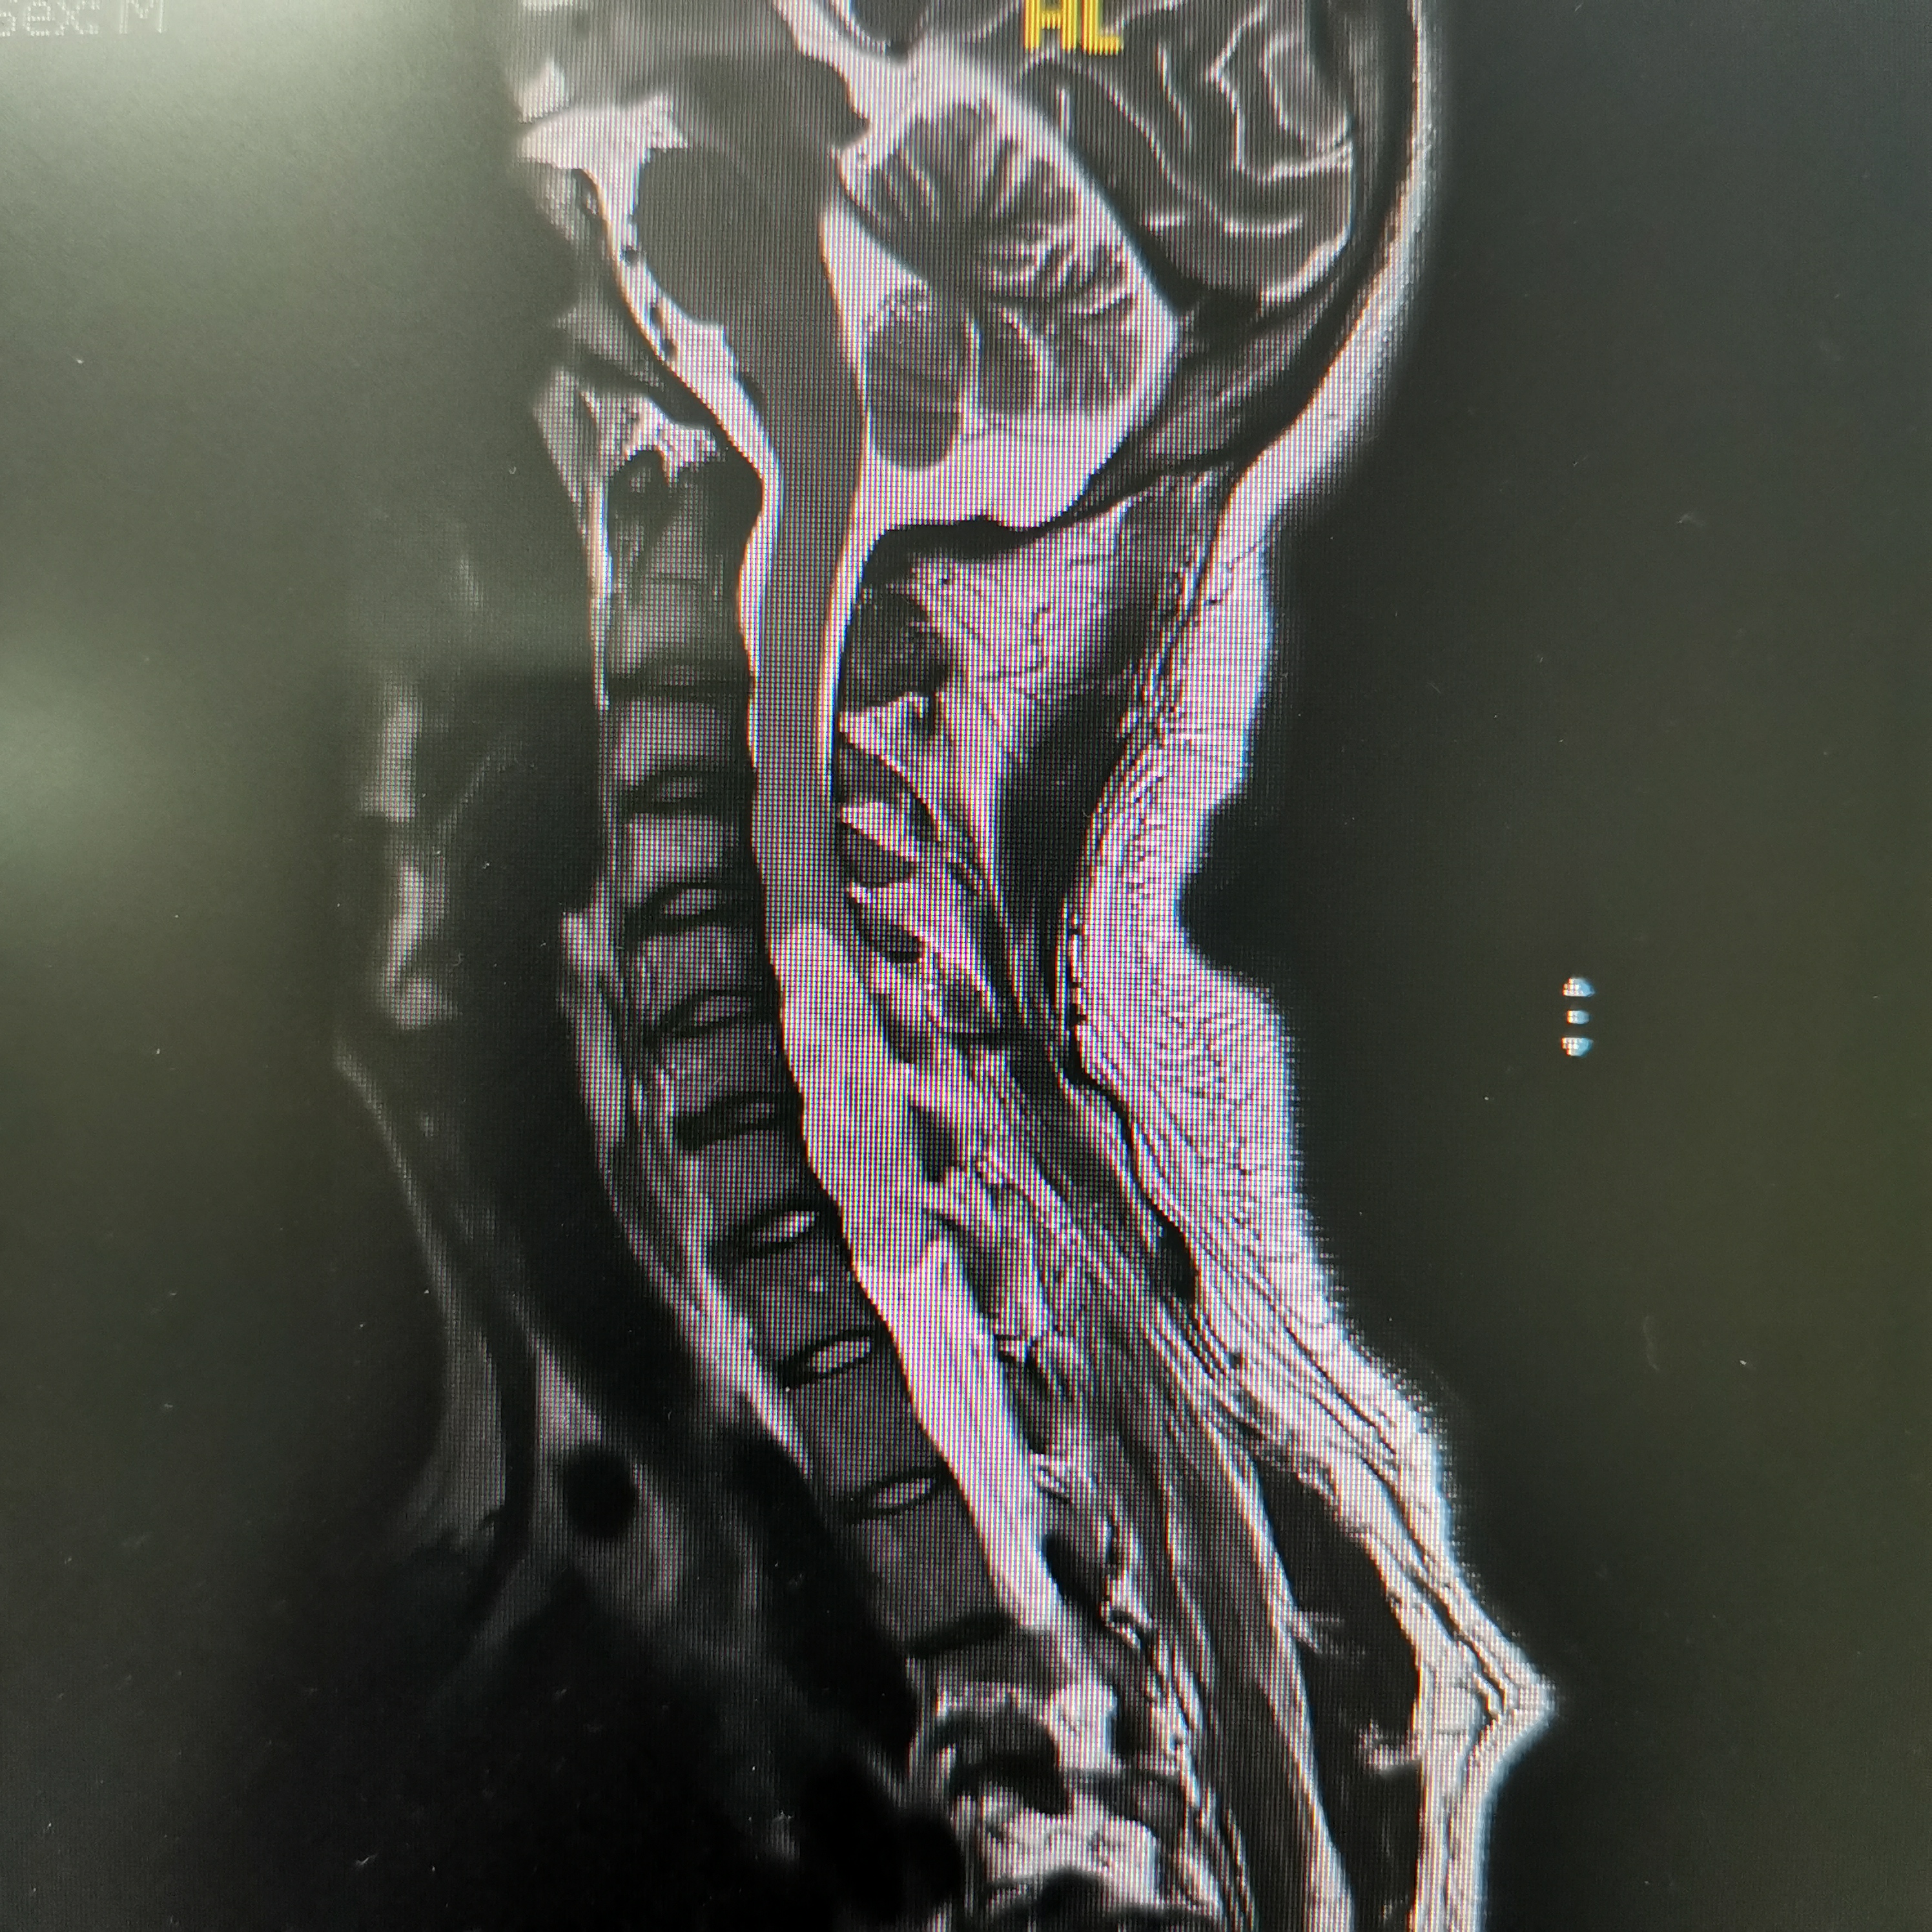

脊髓脊柱-脊髓脊柱肿瘤

神经纤维瘤病的治疗需要综合考虑患者的病情、症状、年龄、身体状况等因素,制定个性化的治疗方案。